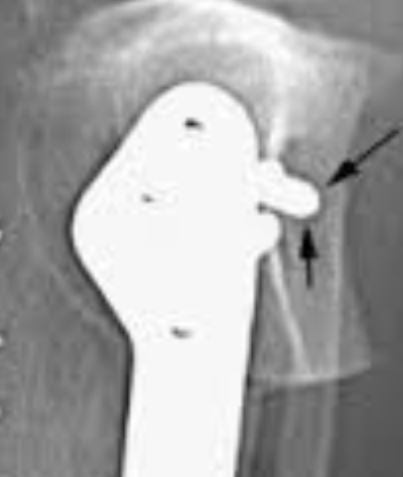

7

Q

Artifact? Fix?

A

Up side down or distance decentered on a focused grid.